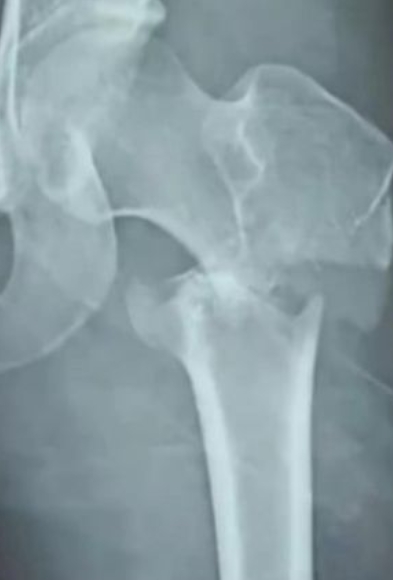

據《ETtoday》報導,這件事情發生在中國,一名重慶的17歲舞蹈學生,一直都希望可以在大學考上舞蹈系,完成自己成為優秀專業舞者的夢想。然而日前在一間舞蹈學習機構,練習柔軟度的時候,突然發出一聲巨大的聲響,不少人都以為是有椅子折斷,這名學生當下也不斷四處張望,想說是不是什麼東西壞的,結果發現,四周的同學都在看自己,接著一股痛楚傳來,她才發現是自己的腳斷掉了。

原來在練習柔軟度的時候,自己的腳居然被協助的老師踩斷了。雖然緊急送醫,可是因為傷勢嚴重,加上骨頭碎裂的狀況,雖然動了2次手術後,沒有性命危險,但是卻被醫生告知,如果要像過去一樣繼續跳舞,是沒有可能了,讓她整個人陷入人生的黑暗中。然而誇張的是,老師跟教育機構的回應,卻讓她們心碎。